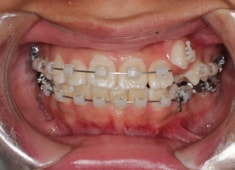

治療開始から5ヶ月後